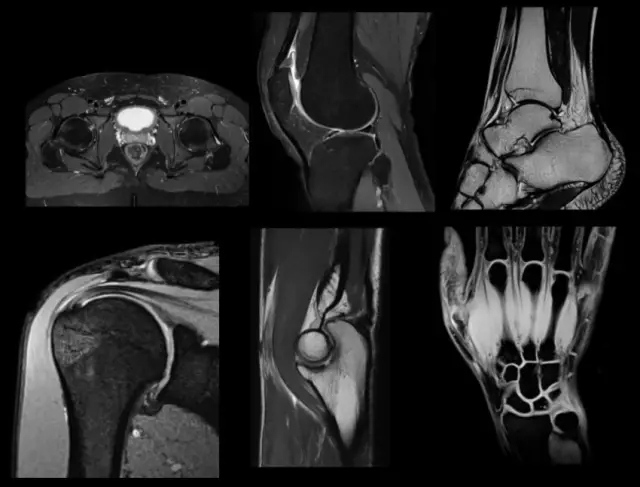

腦卒中應(yīng)用

中醫(yī)在腦卒中的預(yù)防、治療、康復(fù)方面具備全面的顯著療效。聯(lián)影中醫(yī)磁共振搭載多款高級應(yīng)用,能夠輔助醫(yī)生進(jìn)行精準(zhǔn)診斷,為判斷腦梗塞或出血提供更為客觀的判斷標(biāo)準(zhǔn)。

聯(lián)影醫(yī)療發(fā)布業(yè)界首臺中醫(yī)磁共振成像系統(tǒng)

聯(lián)影中醫(yī)磁共振搭載彌散加權(quán)成像技術(shù),可準(zhǔn)確判斷腦卒中分期(左);磁敏感加權(quán)成像可更敏感地判斷梗塞是否伴有出血,幫助醫(yī)生判斷是否進(jìn)行溶栓、抗凝等治療(右)